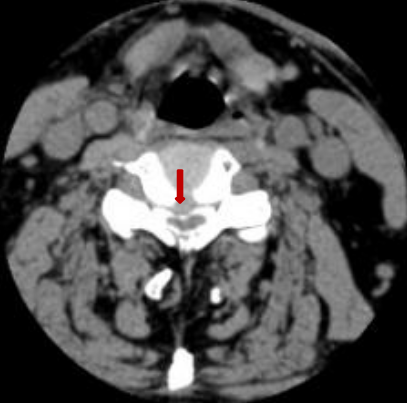

术前脊髓造影后颈椎CT。

颈椎间盘突出明显。